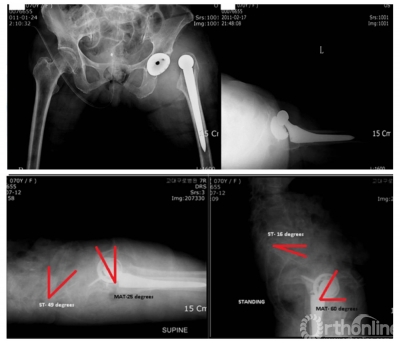

图6 多例病例显示脊柱-骨盆固定后骨盆前倾,髋臼前倾角变小

脊柱-骨盆力线不良的患者髋臼假体过度前倾的患病率高,而且THA术后脊柱矢状面矫正导致髋臼前倾角减小,可能影响稳定性。脊柱融合术前倾的变化与骨盆盆倾斜的变化幅度甚至接近1:1。

图7 AS引起THA术后脱位病例

手术时可根据后倾角度调整髋臼假体置入角度,减小外展与前倾角,防止术后脱位,增加站立位髋关节稳定性的同时,减少了假体与骨的接触面积,以适应变化的脊柱-骨盆力线,避免术后出现髋臼假体过度前倾,以及站立位时发生后方撞击、前方不稳甚至前脱位等并发症。对于合并脊柱后凸畸形的AS患者,除非畸形过于严重,应首选脊柱矫形术,再行THA。